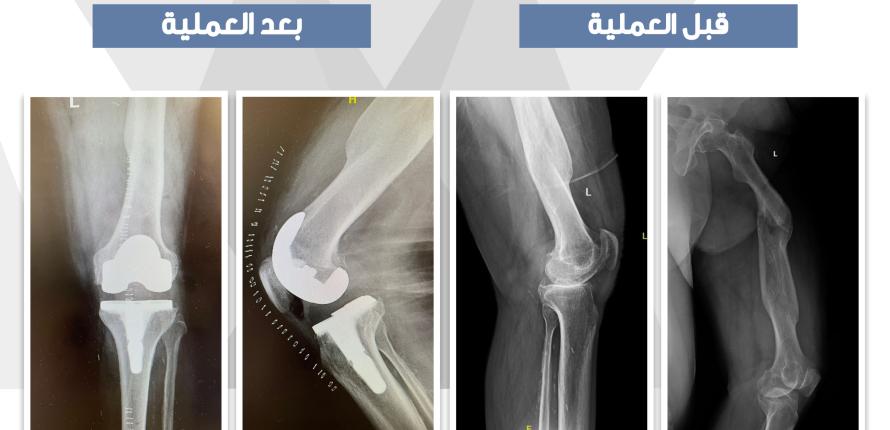

«الروبوت» يعيد الحركة لمريض ستيني بـ «طبية» جامعة الملك سعود 27 Jan 2022 بواسطة رسالة الجامعة كتب – مساعد الغنيم تصوير – توفيق الغامدي تمكَّن فريق طبي مختص بالمدينة الطبية الجامعية في جامعة الملك سعود من إجراء عملية معقدة لاستبدال مفصل الركبة اقرأ المزيد